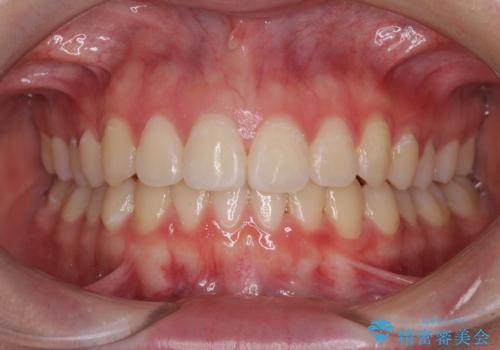

前歯のデコボコを改善 インビザライン矯正

ゴムかけをしっかりと行ってもらい、スッキリとした口元に仕上げることができました。